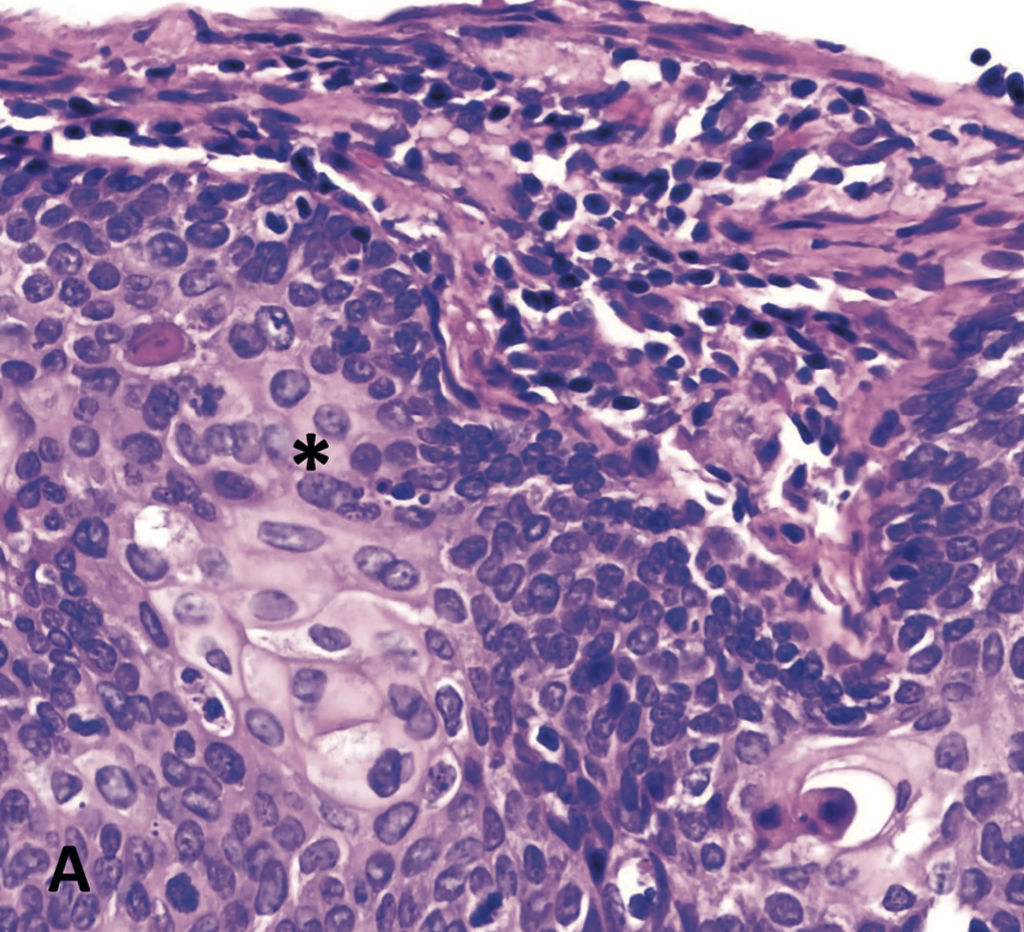

Diego García Prado, Alejandro Readi Vallejos, Gonzalo Campaña Villegas

|

|

|